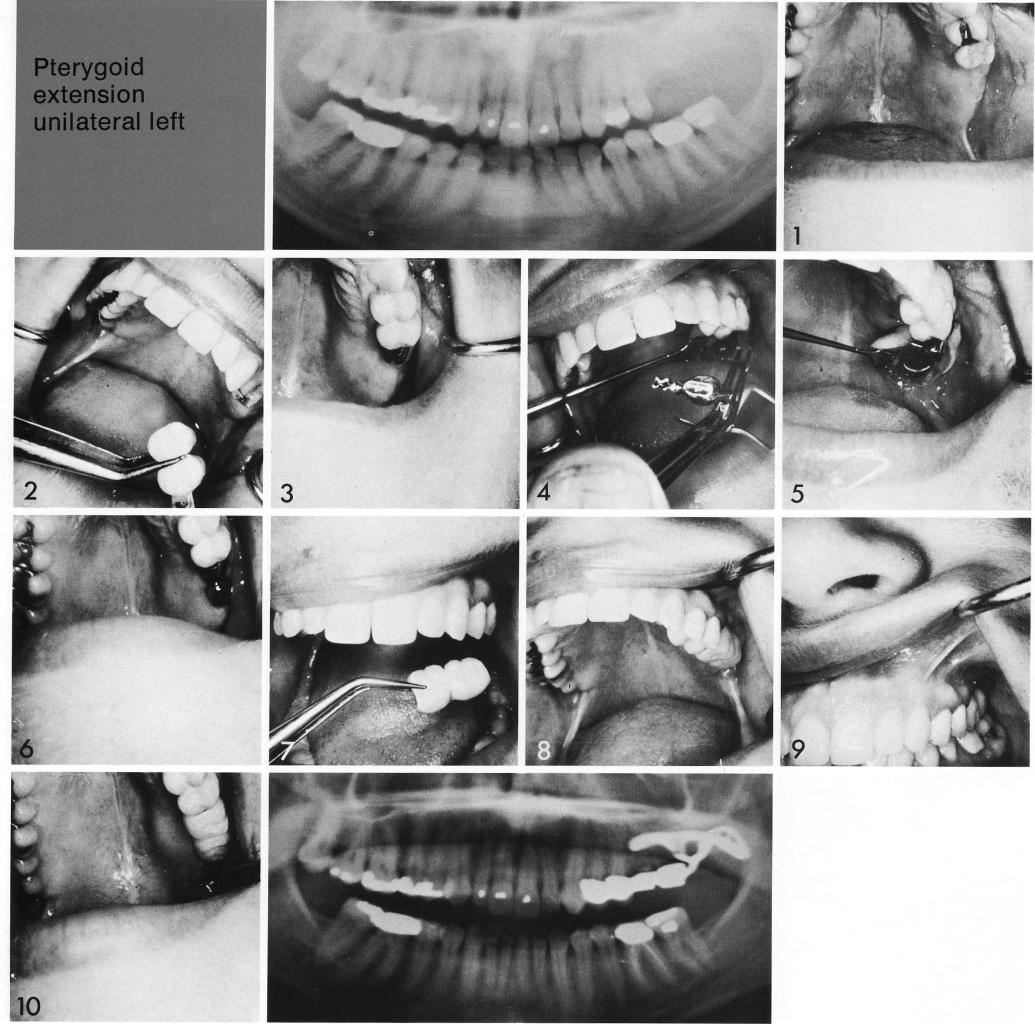

A pterygoid extension implant need not be large or its use limited to cases where bone loss has been dramatically extensive. In this young person (1), the sinus had ballooned backward and downward into the tuberosity. Two teeth were prepared for inclusion in a splint from which had a cantilevered figure-eight female attachment for the pterygoid extension implant (2,3). The implant was inserted, the male attachment cemented into the figure-eight lock (4-6), and the splint fitted to it (7). With a minimal amount of preparation of natural teeth, a pleasing restoration without a bothersome saddle or clips was securely seated (8-10).

Pterygoid extension unilateral left

1 Maxillary sinus had ballooned backward and downward into the tuberosity